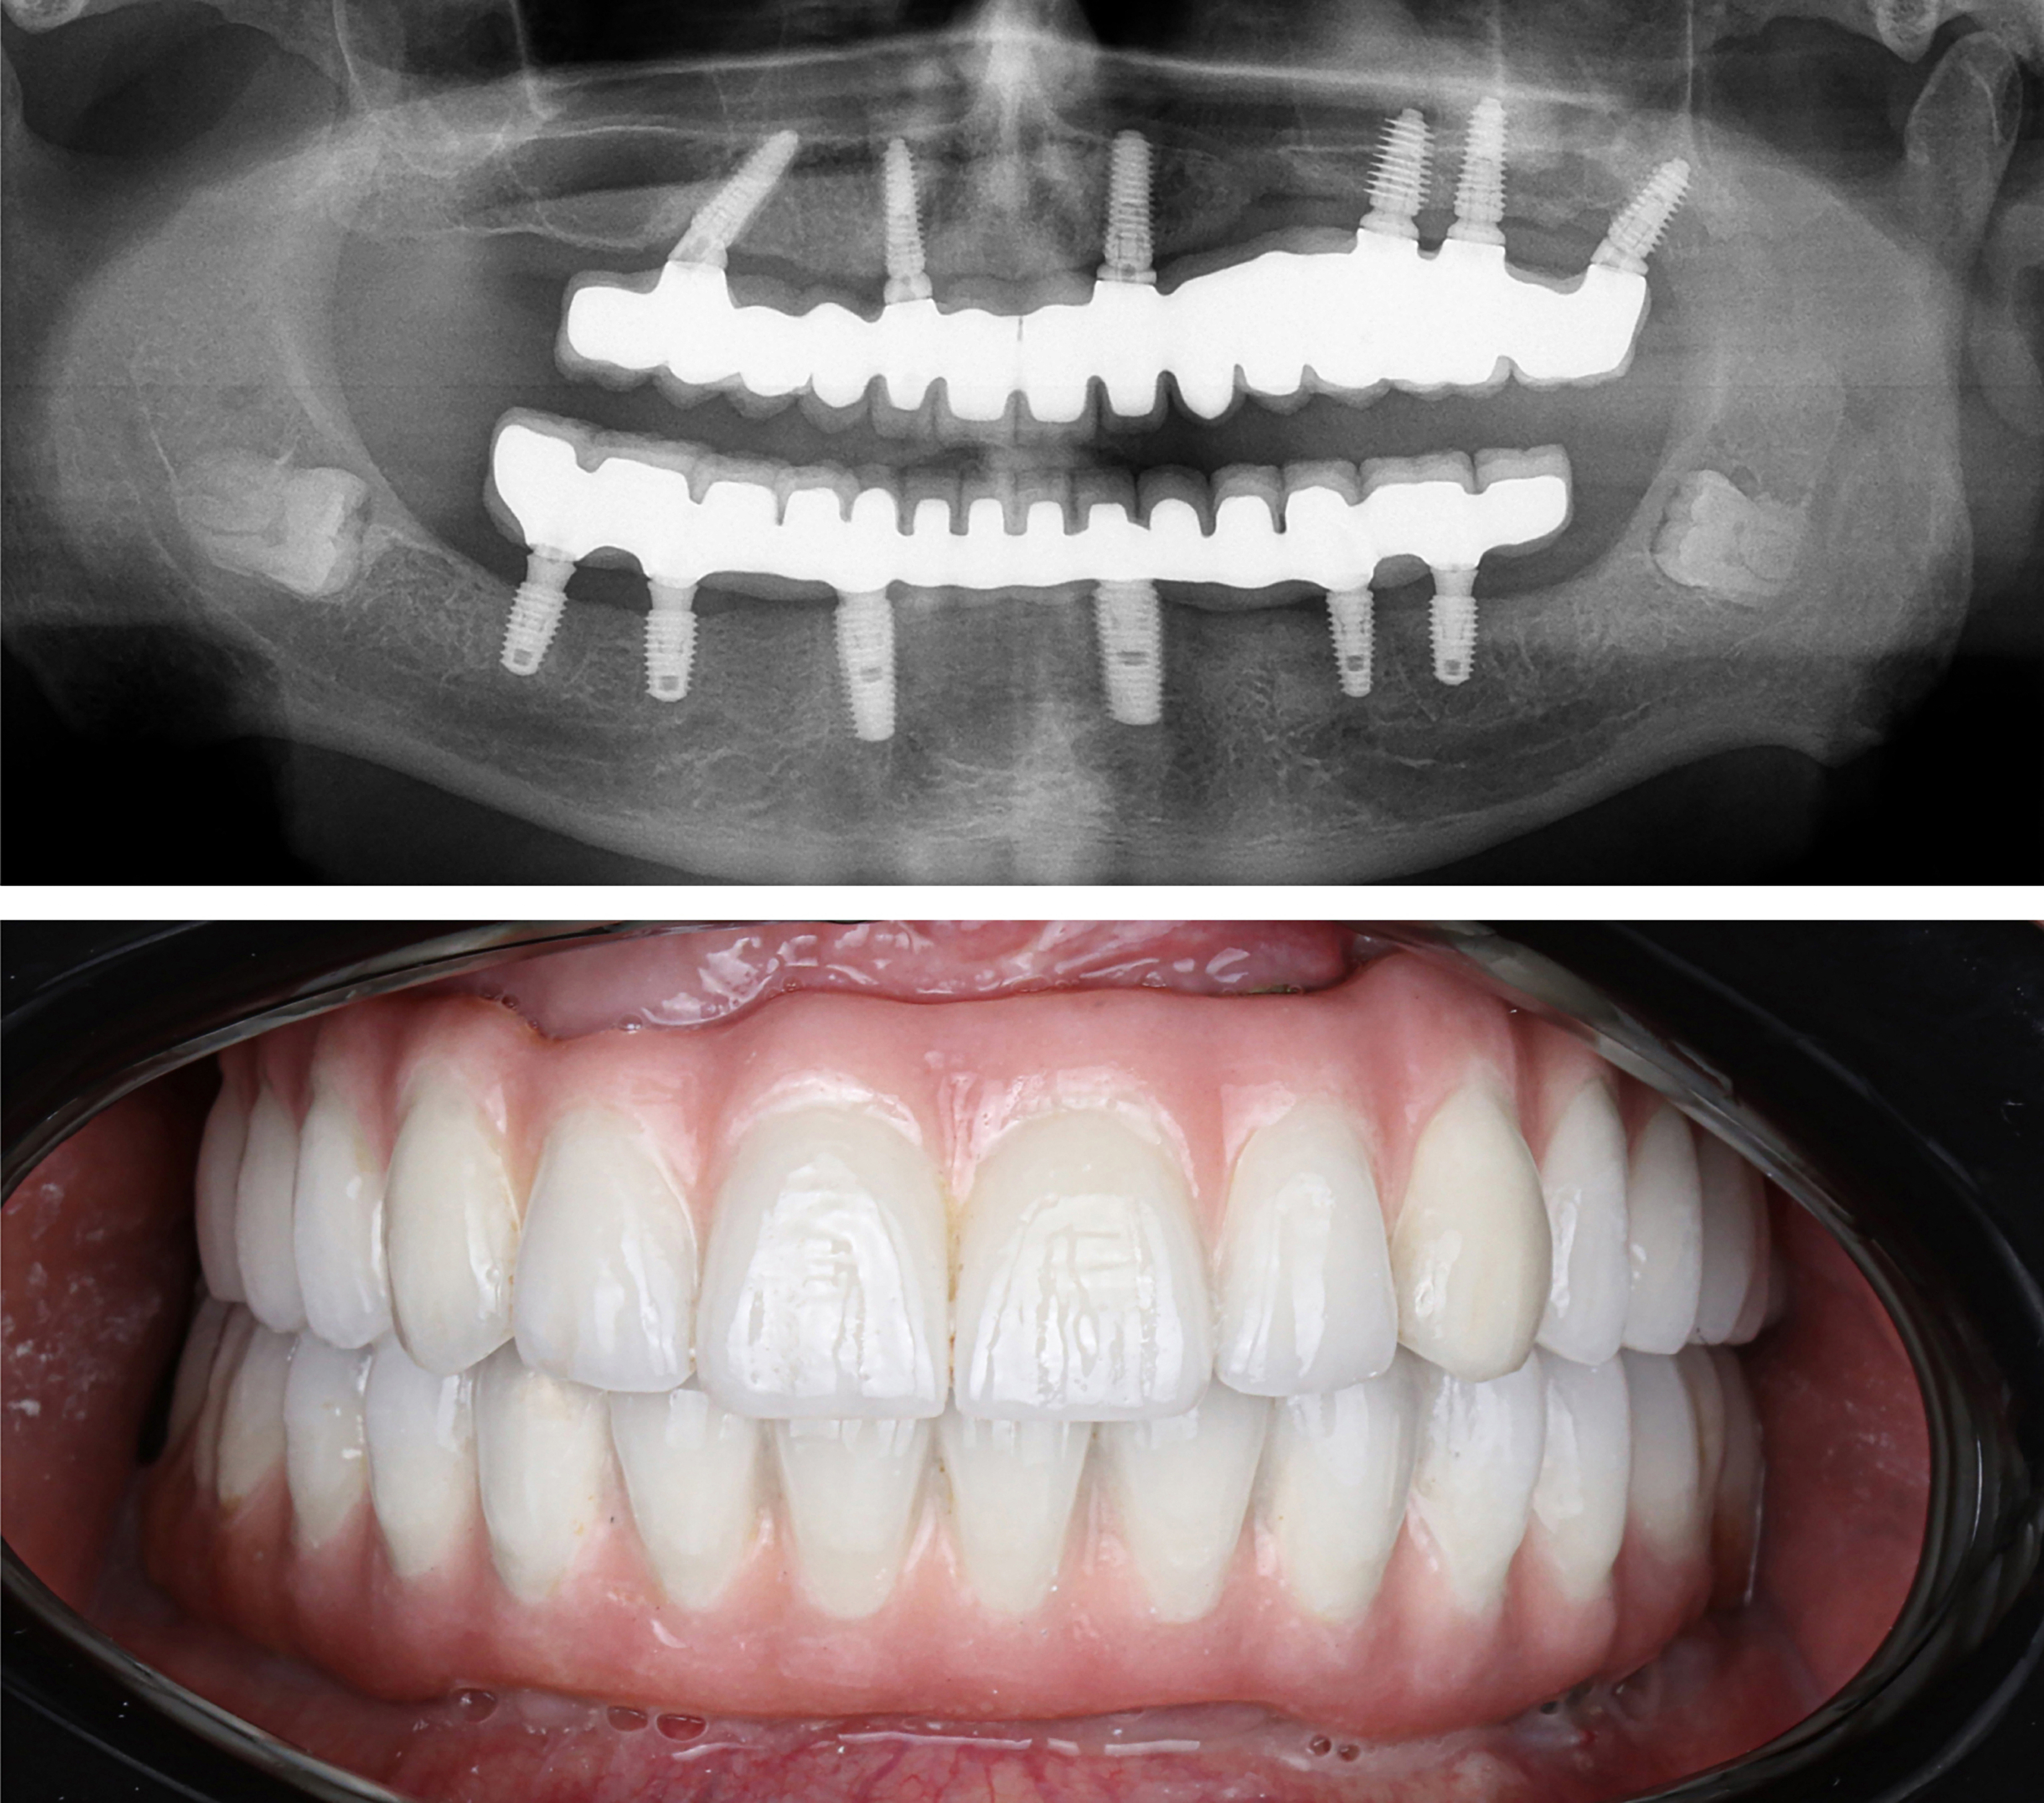

Example transformations achievable with dental implants

So, how do they work?

Every single dental implant consists of three parts - the implant, the abutment, & the crown. The implant is made of medical grade titanium. This part is surgically placed into the patient’s jaw bone and left to heal for 4-6 months afterwards.

This implant piece acts as the foundation for the rest of the tooth. Once the bone around the site has healed, the abutment and crown are placed on top of the implant. The end result is a beautiful, natural-looking new tooth!

Few people will ever be able to tell the difference between your implants and your real teeth.